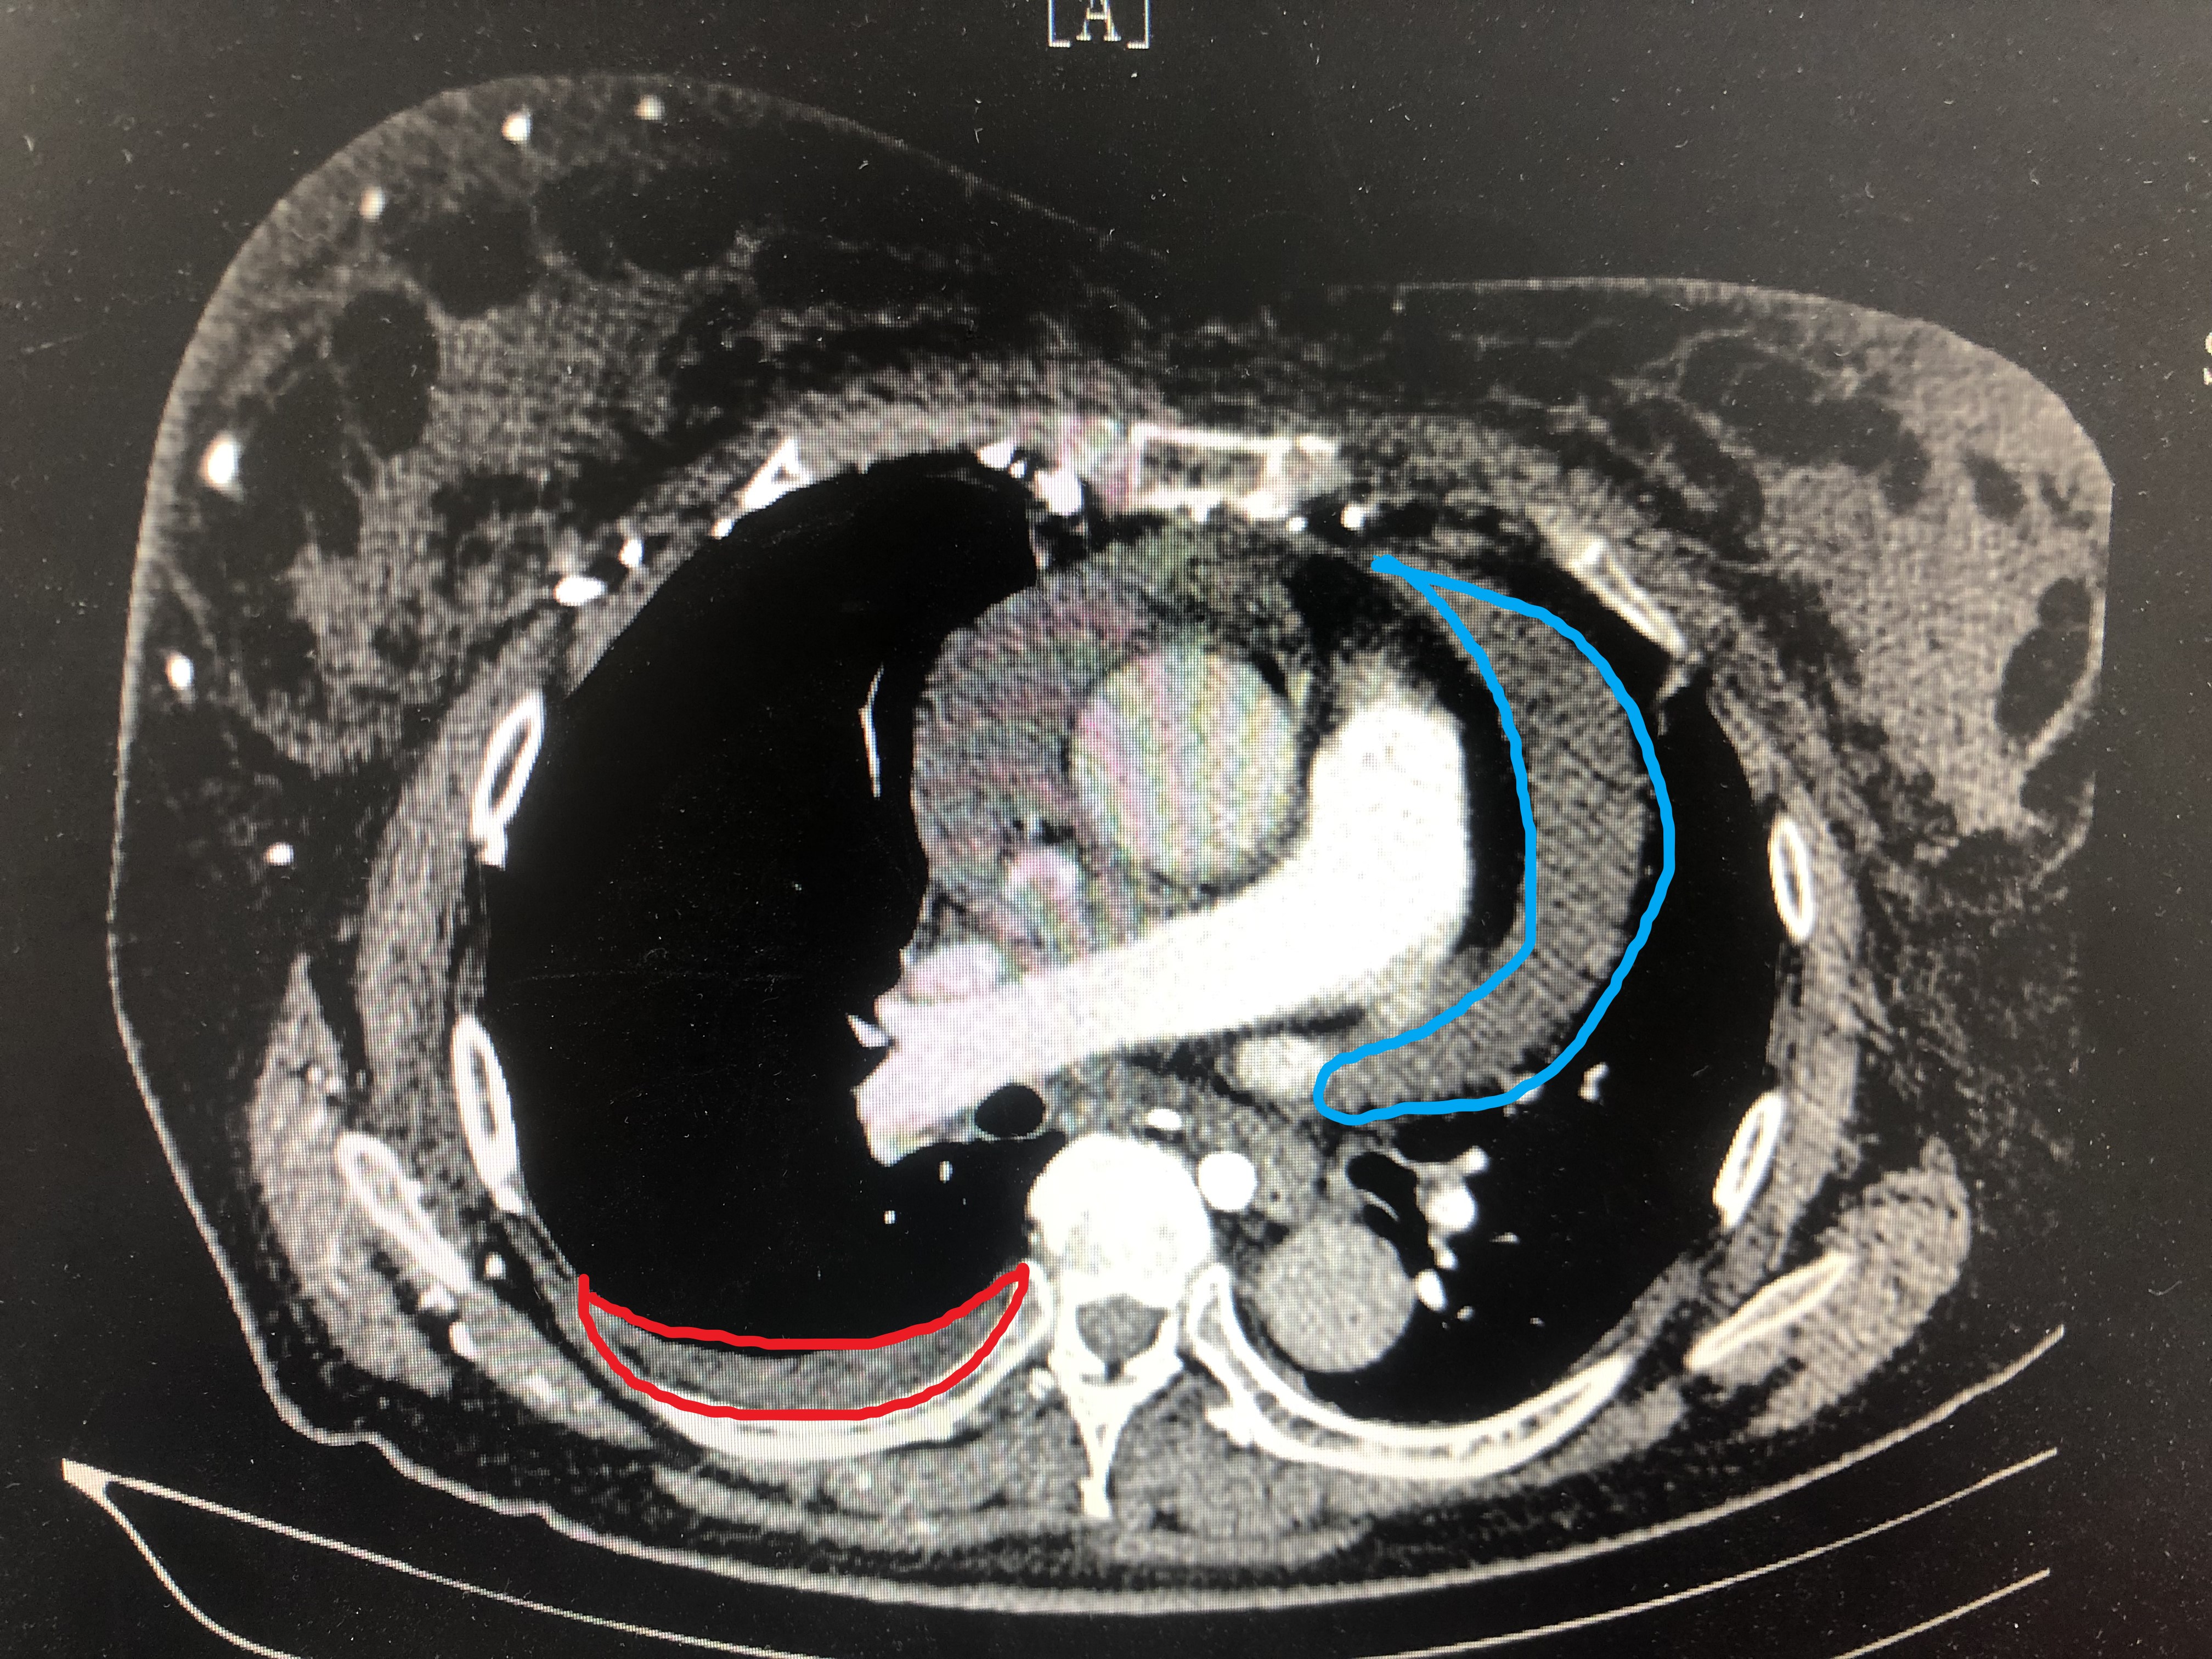

蓝色区域为肺癌转移到心包腔引起的心包积液,红色区域为肺癌转移到胸膜腔引起的胸腔积液